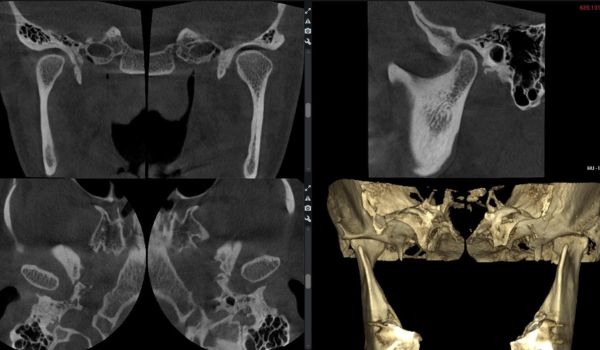

Скронево-нижньощелепний суглоб: стандарти рентгенологічних досліджень для лаборантів